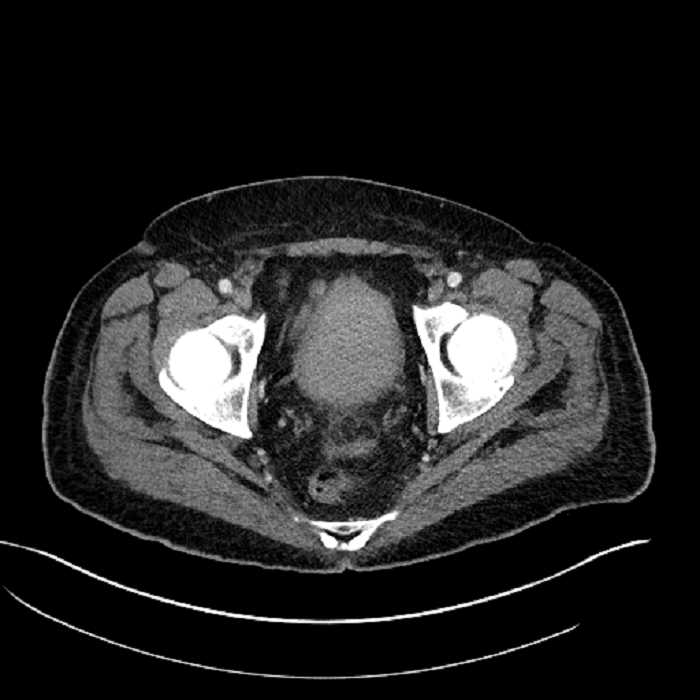

Age: 63

Sex: Male

Indication: Abdominal pain

• High grade stenosis of the left common iliac artery, with the left internal and external iliac arteries remaining patent

• Ankylosis of both sacroiliac joints

• Hepatic abscess

Acute sigmoid diverticulitis complicated by a small contained perforation and a large abscess in the right hepatic lobe. Additional small subcapsular abscesses along the anterior margin of the left hepatic lobe.

High grade stenosis of the left common iliac artery. The left external and internal iliac arteries are patent.

Hepatic abscess showing the double target sign with low density internally surrounded by a thin inner enhancing rim (red arrow) and ill-defined outer low density rim (yellow arrow). Blue arrow indicates an internal septation. Red arrows: additional smaller subcapsular abscesses. Red arrow: focal contained perforation associated with diverticulitis.